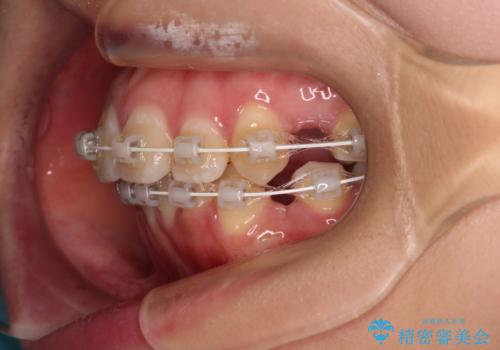

- 矯正装置

- 審美装置

突出感の強い上顎前歯をしっかりと後方移動させるため、上顎の裏側の補助装置(リンガルアーチ)とアンカースクリューを併用しています。

上下左右の第一小臼歯を抜歯して、目立ちにくいワイヤー装置で矯正を行いました。